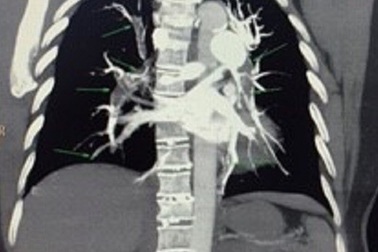

Nguy kịch vì nguyên cả “cây” máu đông trong hệ mạch sau cắt tử cungBuộc phải cắt tử cung để điều trị ung thư, tuy nhiên sau phẫu thuật, huyết khối hình thành và di chuyển tạo thành "cây" máu đông, lấp hệ thống mạch máu gây thuyên tắc khiến người bệnh rơi vào nguy kịch.